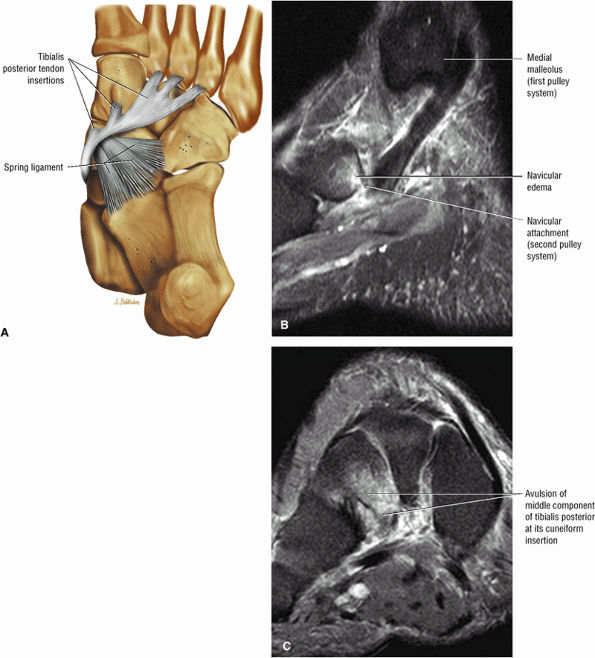

FIGURE 5.135 ● (A) Plantar view color illustration of the distal insertions of the tibialis posterior tendon to the tuberosity of the navicular plantar surface of all the cuneiform bones, the sustentaculum tali, and the cuboid (not shown). The posterior component of the tibialis posterior inserts on the anterior aspect of the spring ligament. (B) Sagittal FS PD FSE image showing the torn insertion of the anterior component of the tibialis posterior into the navicular tuberosity. (C) A coronal FS PD FSE image shows the avulsed middle component, which normally inserts to the cuneiforms, cuboid, and three metatarsal bones. The middle component has a ligamentous function and provides stability to the plantar arch.